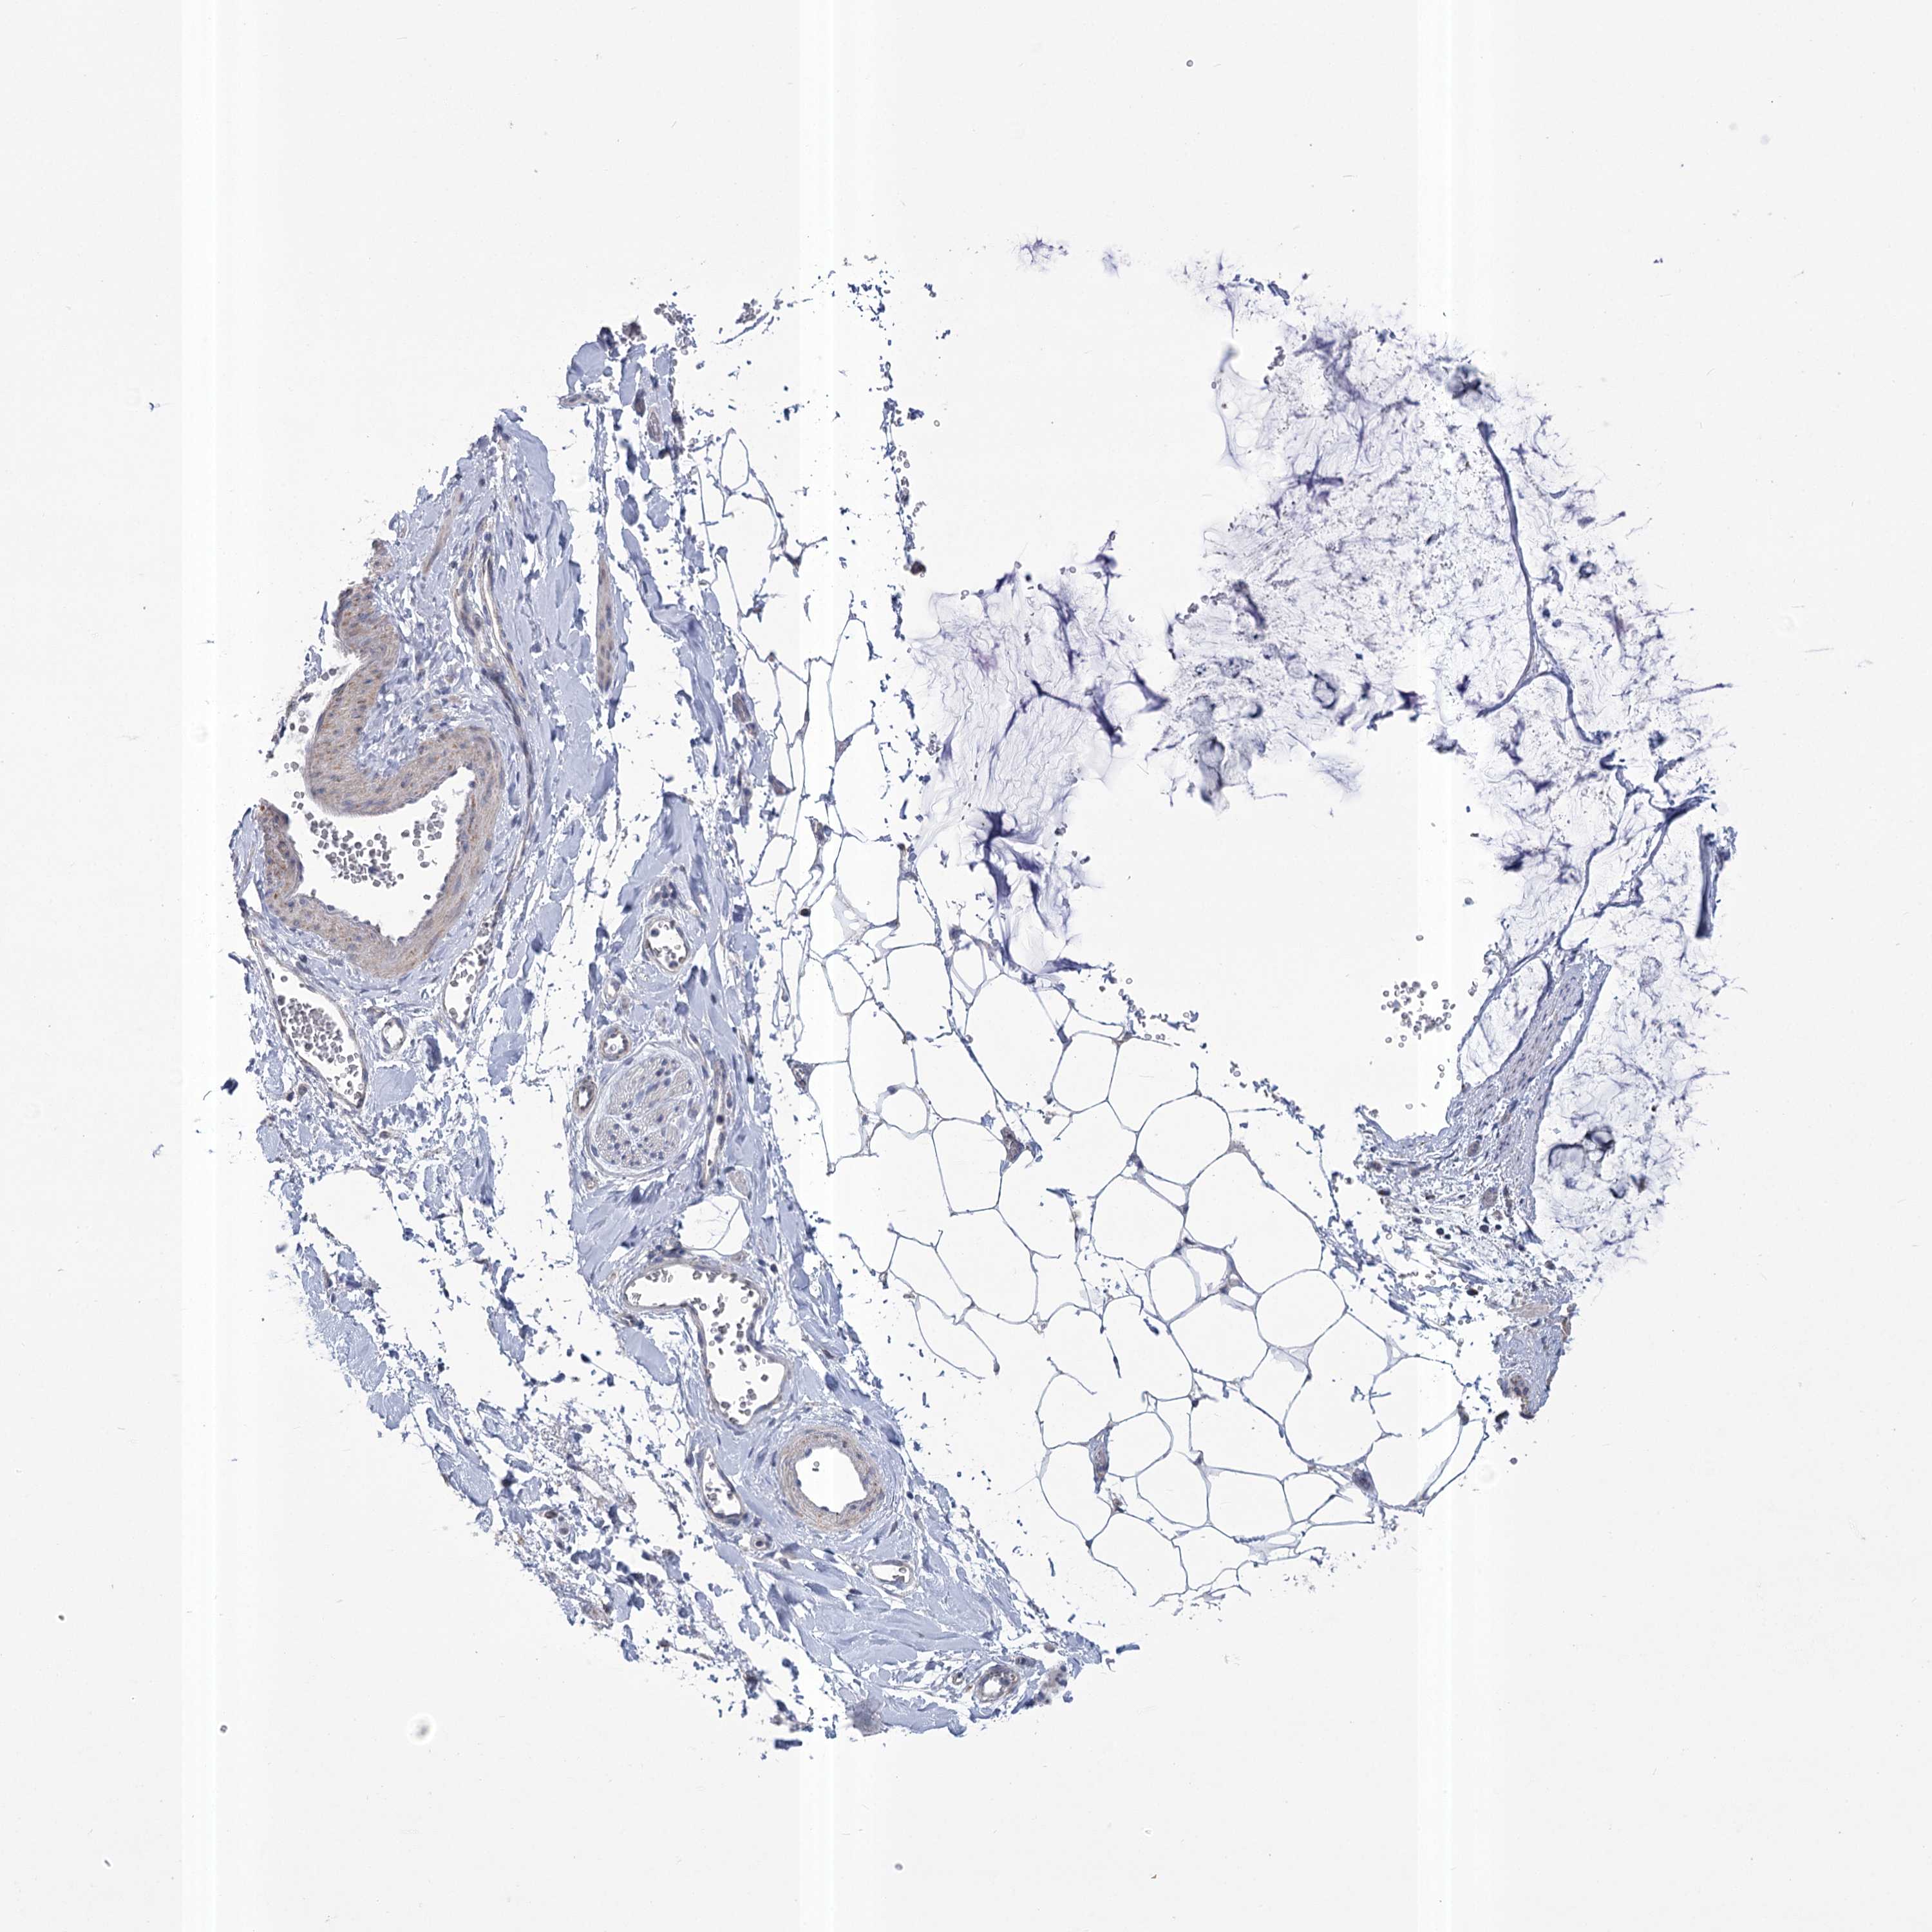

OVARIAN CANCER - Protein expressioni

A mouse-over function shows sample information and annotation data. Click on an image to view it in a full screen mode. Samples can be filtered based on level of antibody staining by selecting one or several of the following categories: high, medium, low and not detected. The assay and annotation is described here.

Note that samples used for immunohistochemistry by the Human Protein Atlas do not correspond to samples in the TCGA dataset.

Antibody stainingi

Antibody staining in the annotated cell types in the current human tissue is reported as not detected, low, medium, or high, based on conventional immunohistochemistry profiling in selected tissues. This score is based on the combination of the staining intensity and fraction of stained cells.

Each image is clickable and will lead to virtual microscopy that enables deeper exploration of all samples and also displays staining intensity scores, fraction scores and subcellular localization as well as patient and tissue information for each sample.

Antibody HPA036744

Antibody HPA036745

Antibody CAB033794

Carcinoma, endometroid

Cystadenocarcinoma, mucinous, NOS

Carcinoma, NOS